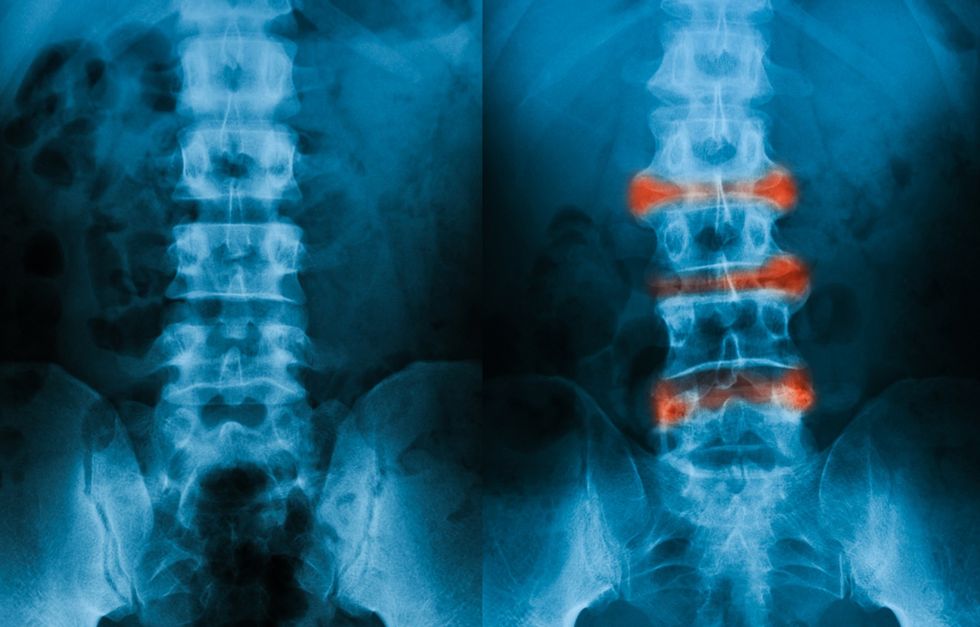

Të dhënat radiologjike fillimisht shihen në nyjet sakroiliake, por ka raste të rralla që nuk preken këto nyje. Ndryshimet radiologjike në nyjën sakroiliake zakonisht janë të dyanshme dhe simetrike. Ato konsistojnë nga dukje e turbullt dhe jo e qartë e kockave subkondrale dhe që pasohen me eruzione dhe sklerozë të buzëve nyjore.

Ndryshimet në pjesën sinoviale të nyjës (dy të tretat e poshtme të nyjës), janë si pasojë e kondritit dhe osteitit të buzëve nyjore.

Erozionet dhe skleroza subkondrale vihen re që në fillim të sëmundjes dhe tentojnë të jenë më të shprehura në anën iliake të nyjës. Progresioni i erozioneve të kockave subkondrale jep pamjen e një 'pseudozgjerimi' të hapësirës nyjore sakroiliake. Më vonë ndodh fibroza, kalcifikimi, urat unazore dhe në fund osifikimi. Pas shumë vitesh vihet re ankilozë e plotë e nyjeve dhe zhdukje e sklerozes.